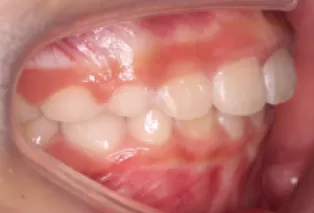

Intraoral photos